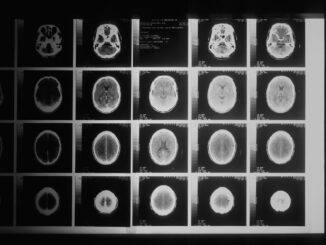

Precision Pediatrics: Children’s Hospital Colorado Forges the Future of Personalized Care In the ever-evolving, sometimes dizzying landscape of pediatric healthcare, precision medicine has truly emerged as a beacon of hope, a guiding light that promises […]